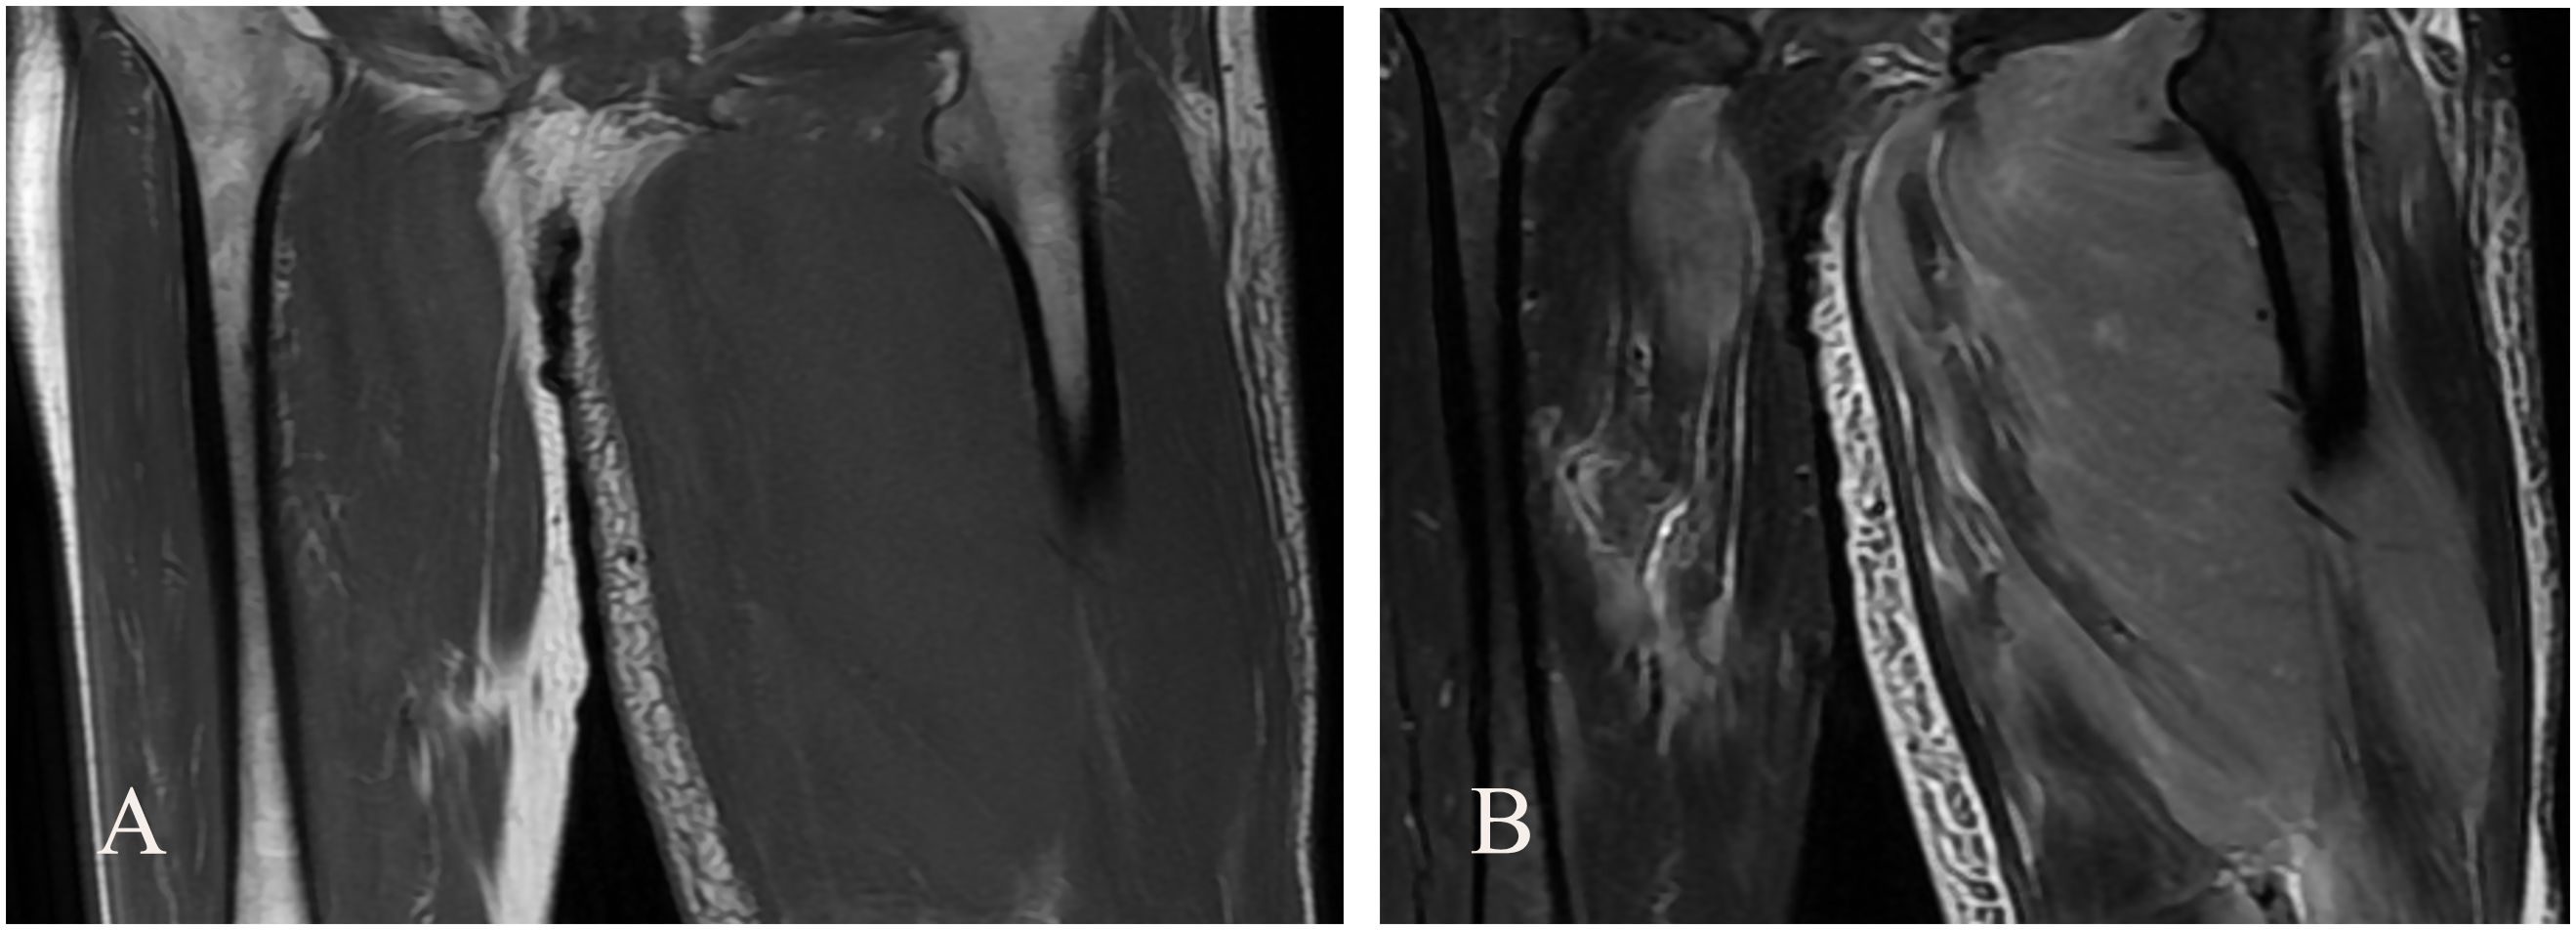

Abstract: Primary non-Hodgkin lymphoma (NHL) of the left lower extremity muscle is a rare exonodal lymphoma, accounting for less than 1% of all exonodal NHL. We report a rare case of intramuscular NHL of the left lower extremity and discuss its clinical features, diagnostic challenges, and treatment strategies with reference to the literature. The patient, an adult male, was treated for sudden swelling and pain in the left lower limb. Ultrasound examination revealed hypoechoic myometrium (hematoma considered), and ultrasound-guided puncture biopsy confirmed "primary CD5 + diffuse large B-cell lymphoma (leg type)"; the patient received 6 chemotherapy, and the symptoms were significantly relieved, but early local recurrence occurred; the clinical manifestations and imaging features of primary NHL in skeletal muscle lacked specificity, and the diagnosis depended on pathology and molecular analysis. Its pathogenesis may be related to direct invasion, hematogenous metastasis or primary muscle lesions. CD5 + diffuse large B-cell lymphoma (DLBCL) is aggressive and R-CHOP combined with radiotherapy is recommended, but prognosis is affected by age, LDH levels, and molecular characteristics such as TP53 mutations. Primary non-Hodgkin lymphoma in the muscle of left lower limb is very rare. It is difficult to diagnose it by imaging examination alone. It needs to be considered comprehensively by combining various examination methods. Pathology is the gold standard for diagnosis. Radiotherapy and chemotherapy are the first choice for treatment. It is very important to formulate reasonable treatment plan according to the results of pathology and molecular analysis.